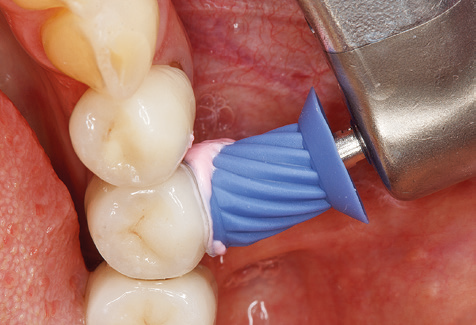

Following machine cleaning of the tooth and implant surfaces, the surfaces of the natural teeth are cleaned manually using standard hand instruments. When performing manual cleaning, particular attention must be given to maintaining the correct angle of application, appropriate sharpness, good support and working with the curette from apical to coronal. Either titanium or carbon curettes should be used for post-cleaning of the implant structures (Fig. 8). In addition to the use of ultrasonic devices, power jet devices can also be used in conservative dentistry. However, it must be taken into consideration that these procedures are not suitable for removing hard deposits and thus they cannot replace the use of hand instruments and ultrasonic instruments completely. In all cases, cleaning is followed by mechanical polishing of the accessible tooth and implant surfaces with polishing cups and polishing compounds (Fig. 9).